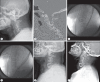

Methods: Twenty-three patients with single level cervical facet fracture and dislocation who were subjected to the anterior approach alone following immediate intraoperative reduction under general anesthesia from March 2013 to December 2017 were enrolled in this study. Neurological status, clinical outcome, and radiological studies were evaluated preoperatively, postoperatively, and during the follow-up period.

Results: The cohort comprised 15 men and eight women with a mean age of 57 years (from 24 to 81). All patients were operated on within the first 8 hours following the injury. After gentle manual reduction or closed reduction with Gardner-Wells traction, under general anesthesia monitored by somatosensory-evoked potentials, all operations were successfully completed using the anterior approach alone except in two patients, who had a risk of over-distraction. In them, a satisfactory gentle manual reduction or closed reduction was not possible, and required open posterior reduction of the locked facets followed by anterior cervical discectomy and fusion. In one patient, screw retropulsion was observed in 1 month after surgery. There were no reduction-related complications or neurological aggravations after surgery. All patients showed evidence of stability at the instrumented level at the final follow-up (mean follow-up, 12 months).